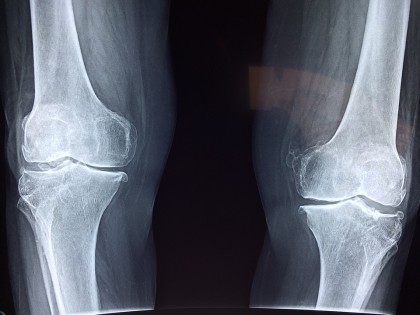

Artrită la genunchi

Artrita genunchiului este o afecțiune care poate îngreuna mersul. Se manifestă prin umflarea, durerea și rigiditatea articulației.

Până în prezent au fost identificate trei tipuri de artrită care pot afecta genunchiul. Cea mai frecventă este osteoporoza, o afecțiune progresivă care duce la uzarea progresivă a cartilajului articular.